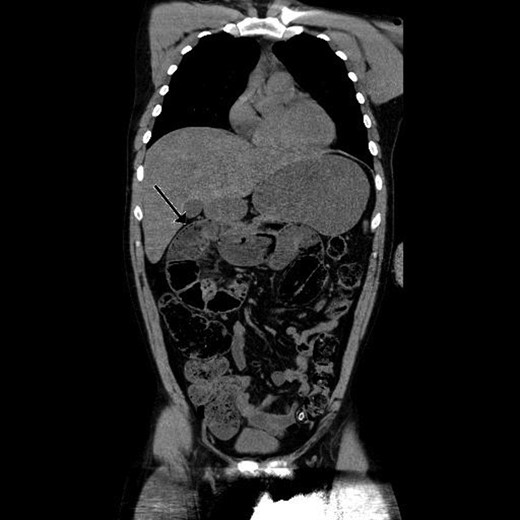

Paraclinical tests showed leucocytosis (10,1 × 109/l) and normal serum lactate. A computed tomography (CT) scan showing gastric retention, encapsulated dilated small intestines in the right upper quadrant with pneumatosis intestinalis and collapsed small intestines distally from this area interpreted as intestinal obstruction (Figs 1 and 2).

Sagittal view of preoperative abdominal CT scan demonstrating encapsulated dilated small intestines in the right upper quadrant with pneumatosis intestinalis.